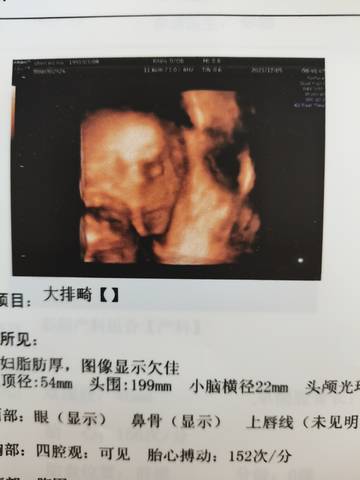

我想知道是男孩还是女孩

journal_insert_pic_1674115913journal_insert_pic_1674115932journal_insert_pic_1674115955journal_insert_pic_1674115986